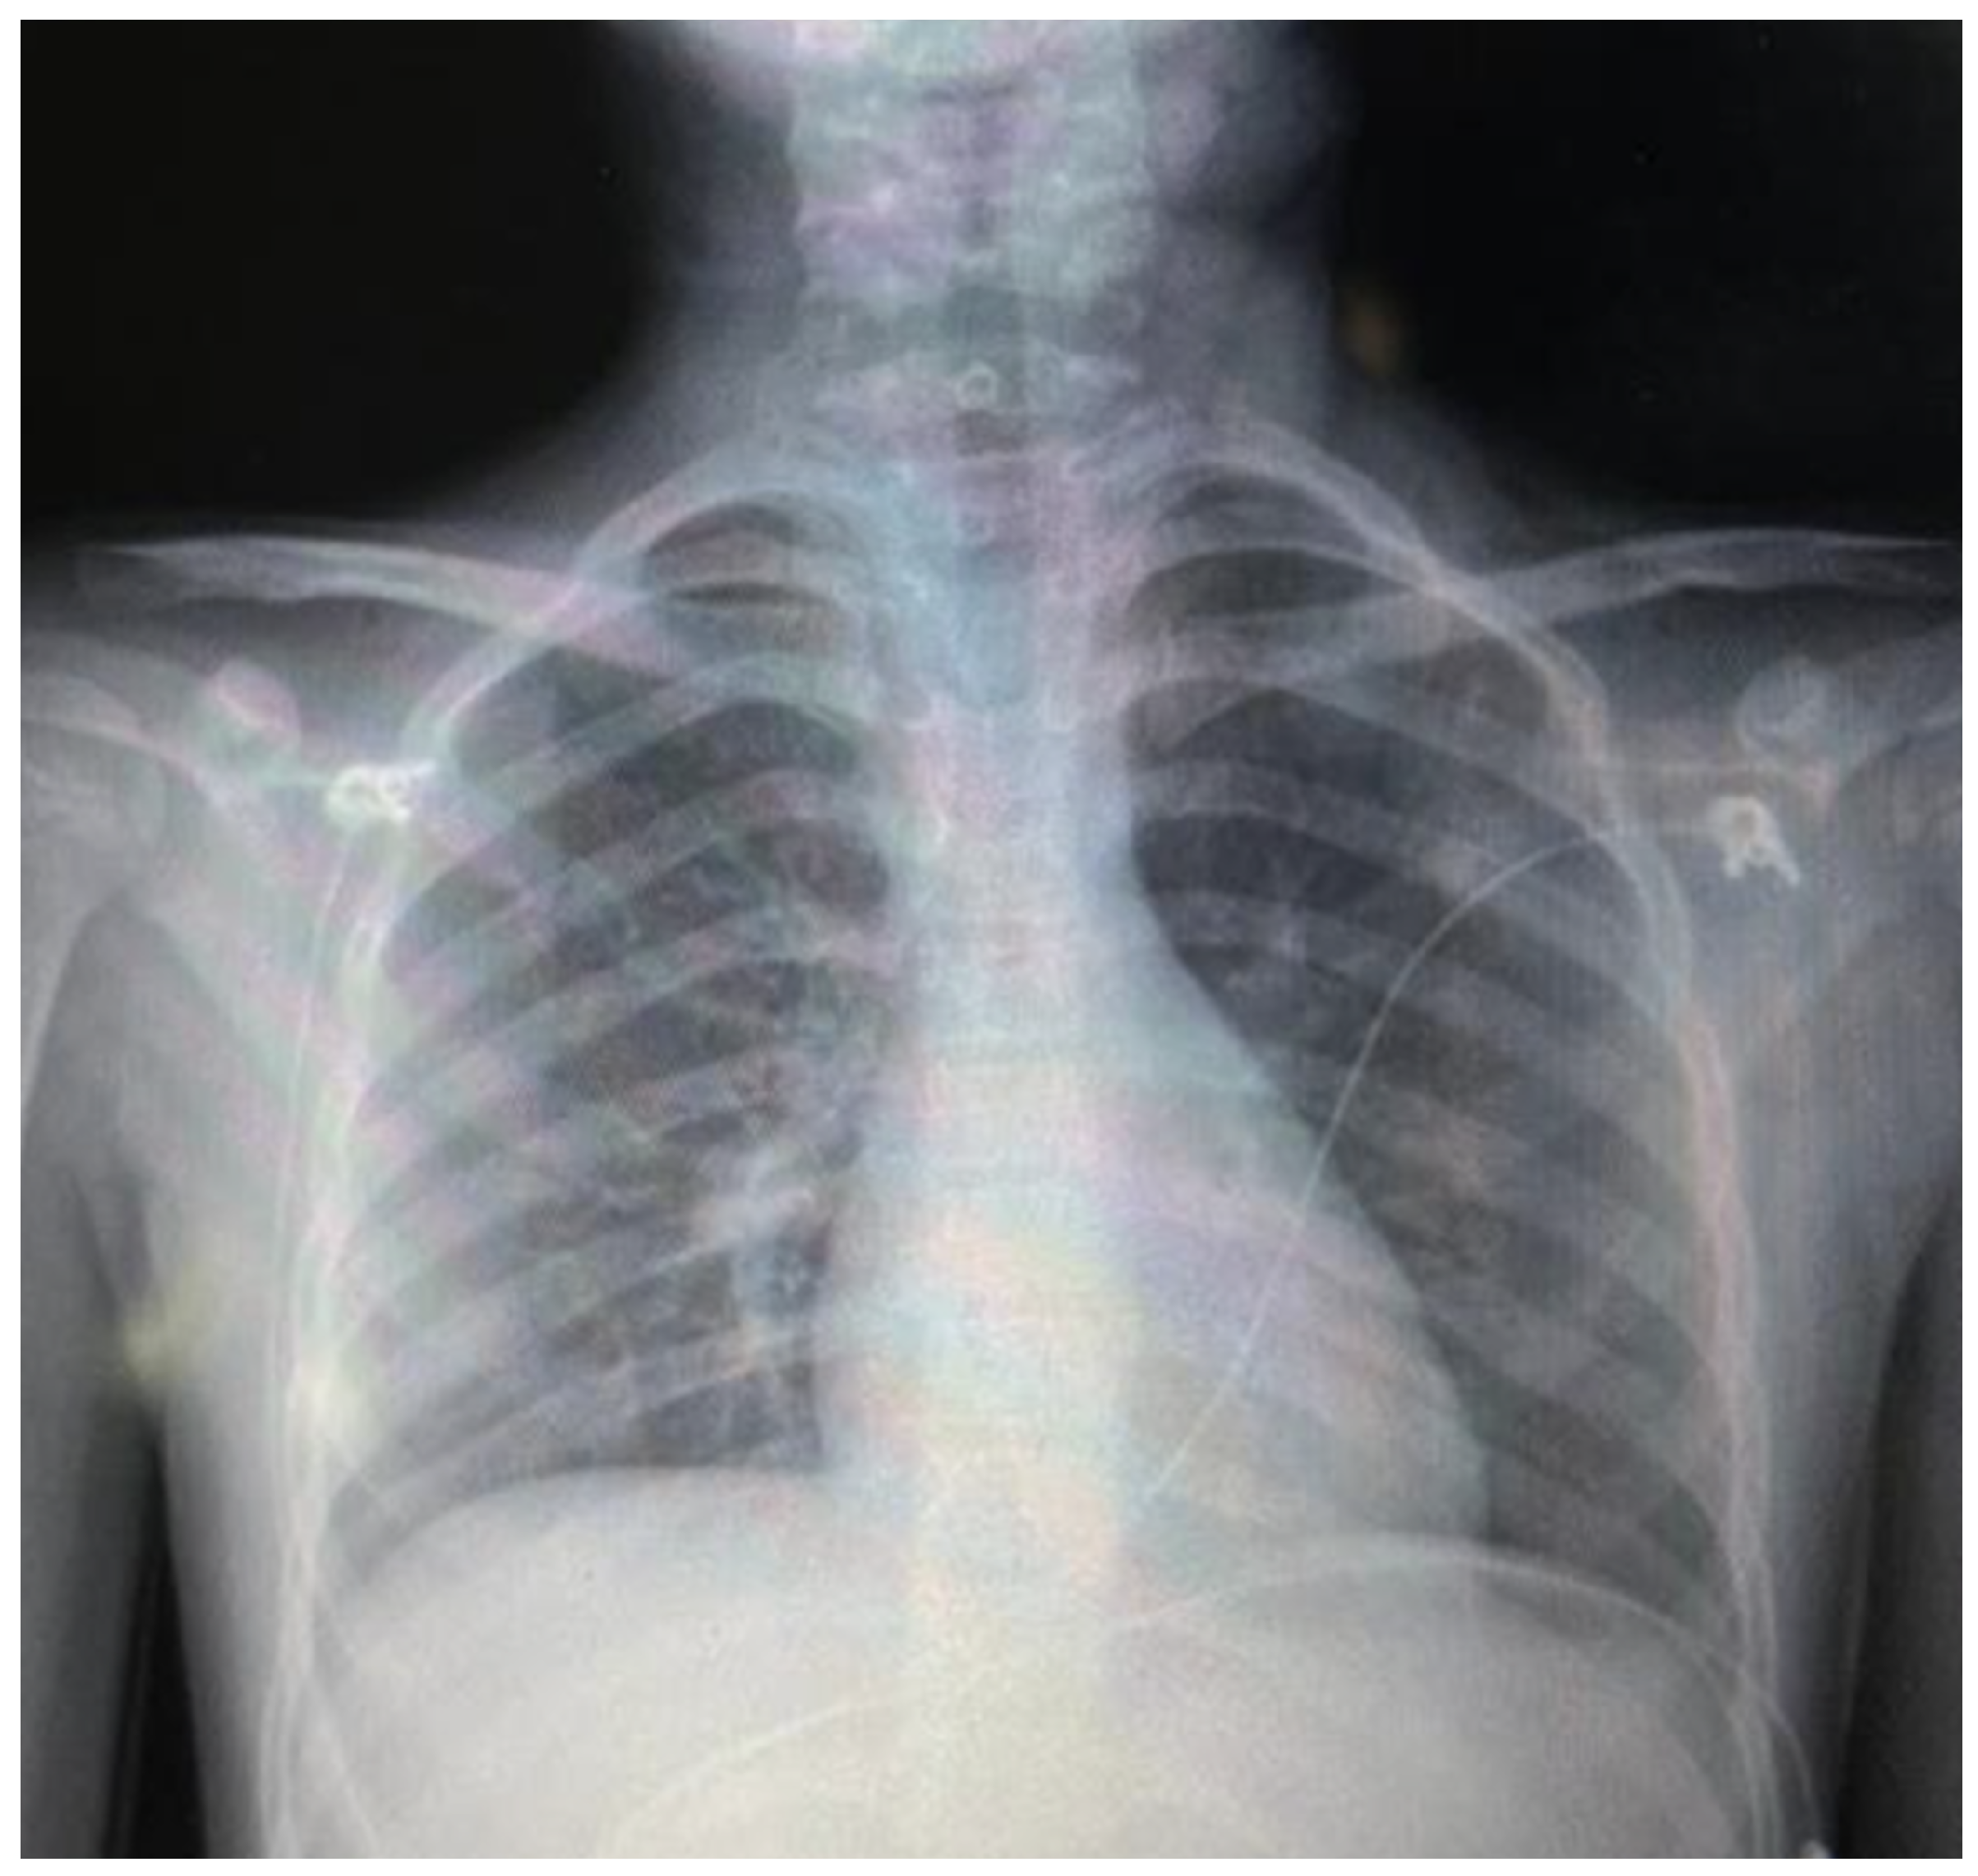

Figure 3. Follow-up posteroanterior chest radiograph (hospital day 3, pre-discharge) demonstrating near-complete resolution of subcutaneous emphysema and pneumomediastinum compared with the admission study (Figure 1). The cardiac and mediastinal contours are now clearly delineated without surrounding radiolucent halos.

The patient remained hemodynamically stable and afebrile throughout hospitalization. Supplemental oxygen was gradually weaned. A follow-up chest radiograph on hospital day 3 demonstrated near-complete resolution of subcutaneous emphysema and pneumomediastinum compared with admission (Figure 3). The patient was discharged on hospital day 3 (February 7, 2026), asymptomatic, tolerating a complete oral diet, and maintaining oxygen saturation above 94% on room air.